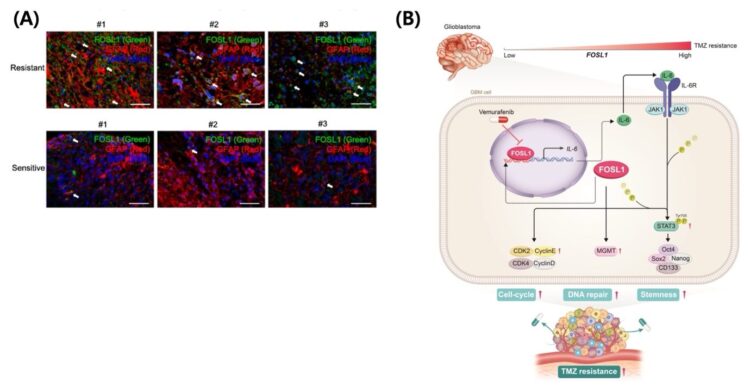

연구팀은 ‘FOSL1’이라는 단백질이 암세포를 ‘줄기세포’처럼 만들어 항암제 내성을 유발한다는 사실을 밝혀냈다. FOSL1이 IL-6/STAT3Tyr705 신호 경로를 활성화해 암세포를 ‘재(再)프로그래밍’(re-programming)하는 메커니즘이다.

FOSL1이 줄기세포 특성(stemness)이나 세포 이동(EMT)을 촉진하는 것으로 이전의 다른 암 연구에선 간혹 거론돼 왔지만, 교모세포종에서 TMZ 내성과 이 단백질을 구체적으로 연결한 것은 이번이 처음. 실제로 환자 데이터 분석 결과, FOSL1 발현이 높은 경우 예후가 훨씬 나쁘고 TMZ 내성이 강하게 나타났다.

더 중요한 것은 FOSL1 기능을 억제하면 줄기세포 특성이 줄고 TMZ에 대한 민감도가 급격히 높아진다는 점이다. 즉, 기존에 약이 안 통하던 ‘내성 암세포’를 다시 치료가 가능한 상태로 되돌릴 수 있다는 의미다.